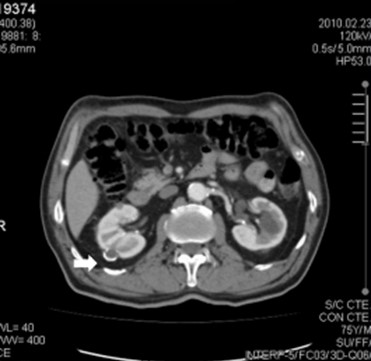

La Categoría IV presenta captación de un componente sólido intra quístico, muestra realces nodulares fuera de la pared y de los septos interpuestos en el área quística compleja, calcificaciones gruesas, vascularizadas con un importante realce con contraste yodado IV. En realidad, son lesiones malignas con componente quístico. Se trata de neoplasias quísticas, y precisan cirugía y estadificación.(19, 21) (Anexos 11 y 12).